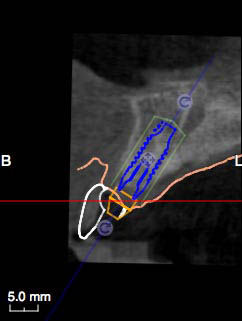

Lateral image after the planning: the software allows the implant to be positioned by verifying the correct prosthetic emergence and angle in respect of the vestibular wall.